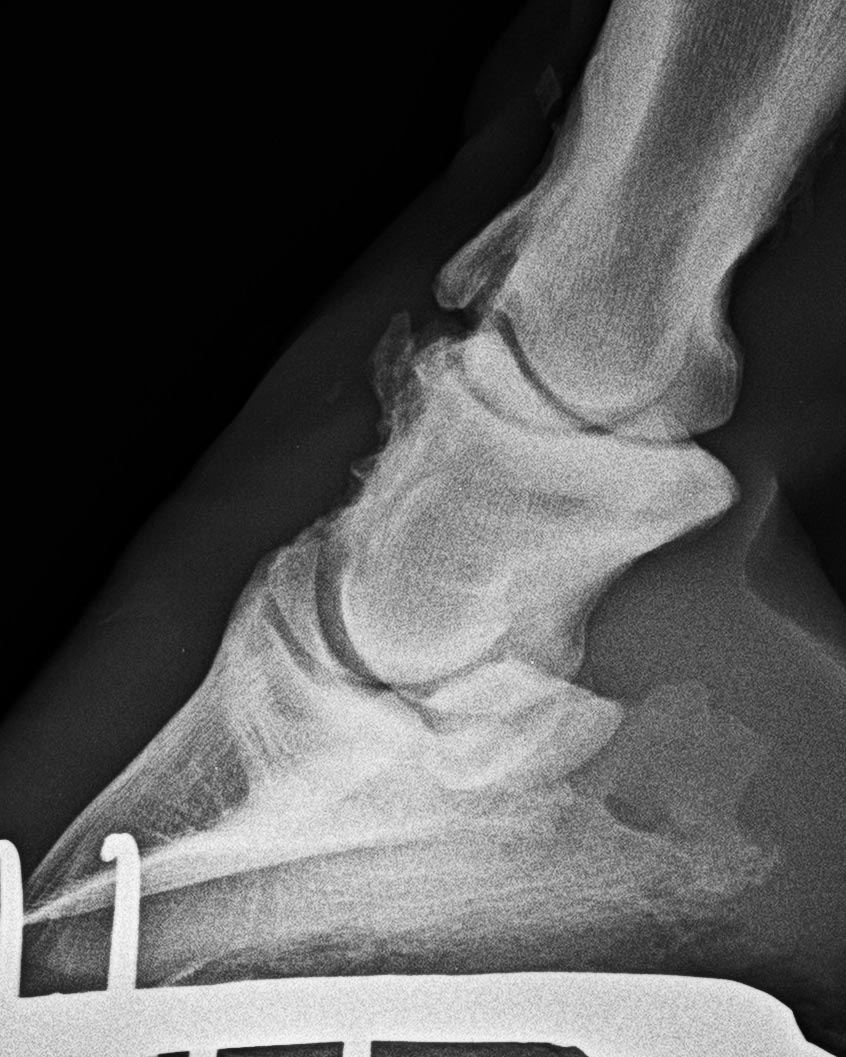

Höchstgradige Krongelenksarthrose (wie im Bild zuvor) Aufnahmerichtung ca. 80°